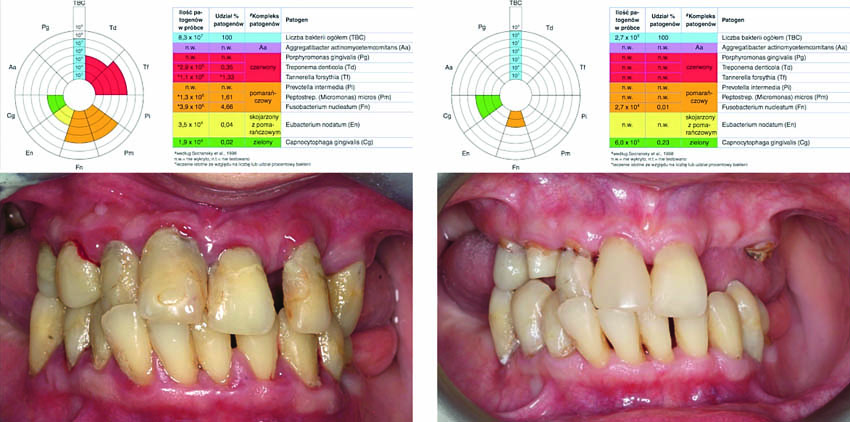

Αναφορά περιστατικού

Μία ασθενής ηλικίας 47 ετών διαγνώστηκε με προχωρημένη γενικευμένη περιοδοντική νόσο, με πολλά ελλείποντα δόντια, απουσία προσθετικών αποκαταστάσεων στην οπίσθια περιοχή του στόματος, περιακρορριζικές βλάβες και μία ατελή ενδοδοντική θεραπεία. Η ασθενής χρειαζόταν μία εκτεταμένη και διεξοδική οδοντιατρική θεραπεία.

Για να δημιουργηθεί ένα προκαταρκτικό σχέδιο θεραπείας, είναι απαραίτητο να εφαρμοστεί μία αρχική θεραπεία (υγιεινή του στόματος), ώστε να ελεγχθεί η ύπαρξη κινήτρου από πλευράς της ασθενούς να συνεχίσει την πολύ εξειδικευμένη θεραπεία όπως επίσης και για να εκτιμηθεί η πρόγνωση των εναπομεινάντων δοντιών της.

Η λεπτομερής κλινική εξέταση θα περιελάμβανε, μεταξύ των άλλων, στοιχεία σχετικά με το βάθος των περιοδοντικών θυλάκων (ΒΘ), την αιμορραγία κατά την ανίχνευση (ΑΚΑ) και τον δείκτη πλάκας (ΔΠ).

Στην περίπτωση που υπάρχει μία σημαντικά βαρεία νόσος, μεγάλη κινητικότητα των δοντιών και πολλά ελλείποντα δόντια, συνιστάται να διεξάγονται μοριακές-βιολογικές εξετάσεις για να πραγματοποιείται μία ποσοτική αξιολόγηση των περιοπαθογόνων.

Πριν τη θεραπεία, η ασθενής υποβλήθηκε σε διαδικασία υποουλικού καθαρισμού με ξέστρα υπερήχων. Μετά τον καθαρισμό, η κλινική κατάσταση της ασθενούς βελτιώθηκε. Στη συνέχεια, εφαρμόστηκε ένα laser Nd:YAG για την αποστείρωση και την απολύμανση των περιοδοντικών θυλάκων (Εικ. 3 έως 7) και laser Er:YAG για την απομάκρυνση της υποουλικής τρυγίας (Εικ. 8 έως 12).